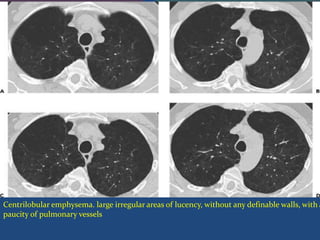

Centriobular Emphysema

 (also called centriacinar or proximal acinar emphysema)

 Selective process characterized by destruction & dilatation of

respiratory bronchioles.

 Emphysematous spaces lie near the center of SPL and the

lung tissue distal to the emphysematous spaces is often

normal . alveolar ducts, sacs and alveoli are spared until a late

stage.

 Upper zones tend to be more severely involved than the

lung bases.

 It is usually found in smokers, frequently in association with

chronic bronchitis.

Centrilobular emphysema. large irregular areas of lucency, without any definable walls, with a

paucity of pulmonary vessels